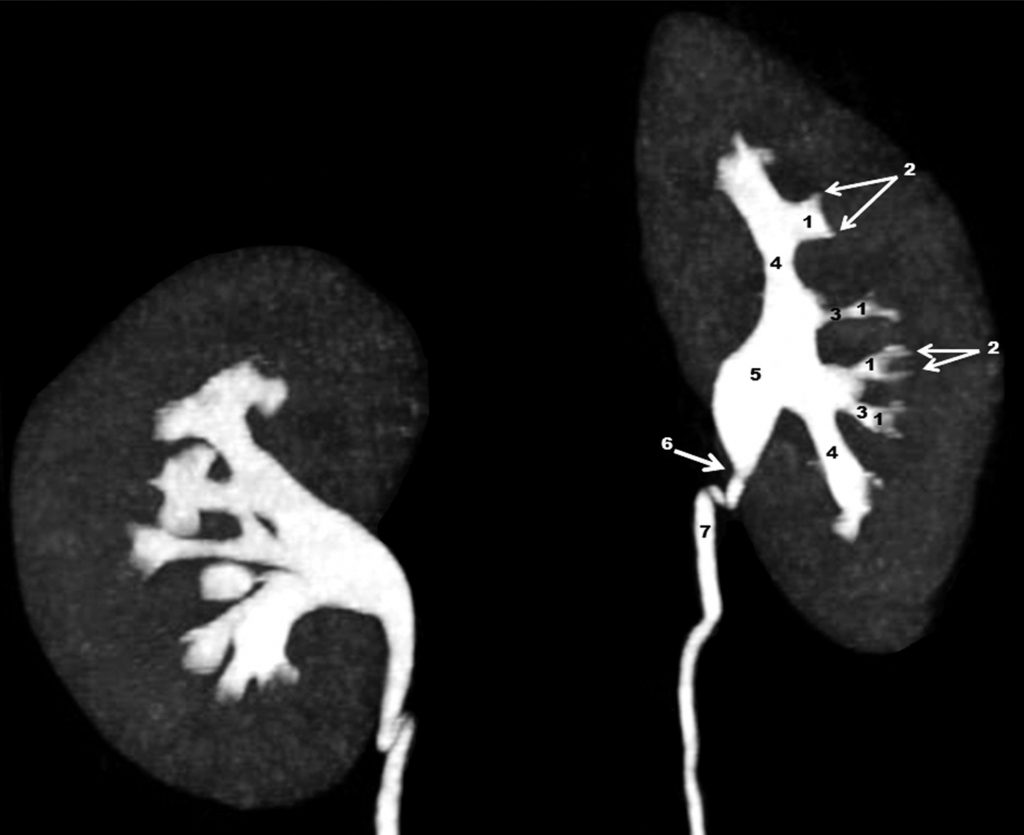

Fig. 19.6. Uroscanner : reconstruction en mode MIP (Maximal Intensity Projection, avec ici suppression des structures osseuses) centrée sur les reins 8 minutes après injection intraveineuse du produit de contraste iodé.

1. Petits calices. 2. Fornix. 3. Tiges calicielles. 4. Grandes tiges calicielles. 5. Pelvis rénal. 6. Jonction pyélo-urétérale. 7. Uretère.

Source : CERF, CNEBMN, 2022.